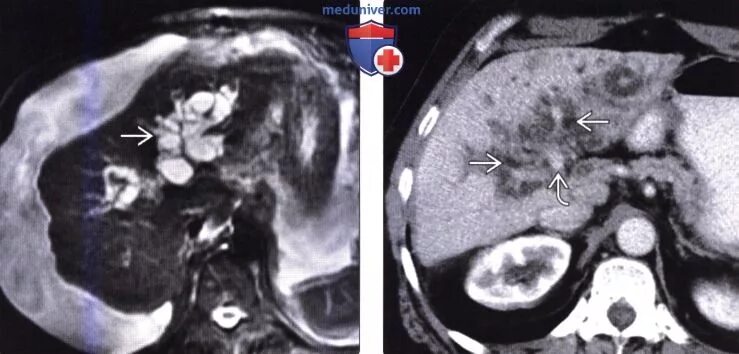

Цирроз на кт